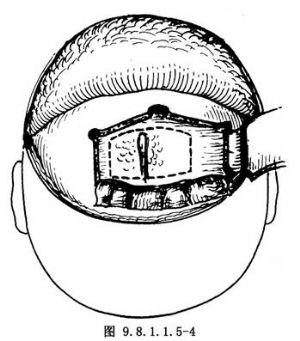

(6)由顱內切開前顱底:顱底骨切開線的位置取決於病變部位和範圍。雙側篩狀板必須包括在內,中部後方切開線應在蝶骨平板,向側方過篩後即應向前轉。若無明顯腫瘤侵犯該區,向側方切開線應在蝶骨小翼與額骨眶板連接線區,以防視神經損傷。若擬保留健側眶內壁,則顱內切開線在篩狀板外側以外0.5cm處,切入篩竇。沿此線縱形切開篩竇頂,中、上鼻甲根部一併切下,而眶內壁得到保留。若擬切除眶內壁,則顱內切開線在眶區內中1/3交界處。患側或病變較重側切開線分以下幾種情況:①保留眶內容型,切開線於眶區中內1/3交界處,眶內壁必須切除;②不保留眶內容型,切開線可外移到眶頂中部,或全部切去眶頂;③腫瘤侵犯較廣,需要聯合切除中顱底者,向側方切開視神經管,切除蝶骨嵴,顯露眶上裂,並沿眶上裂後外緣到中顱底,再向側方至中顱底側壁,根據病變範圍切開骨板,上升至翼點,內到額骨前壁。前方切開線沿額骨垂板下部切入額竇,進而切開額竇底,與鼻腔溝通。翻骨瓣時額竇已暴露者,咬去額竇後板,使額竇底能得到更好的顯露。至此顱內操作完成(圖9.8.1.1.5-4)。